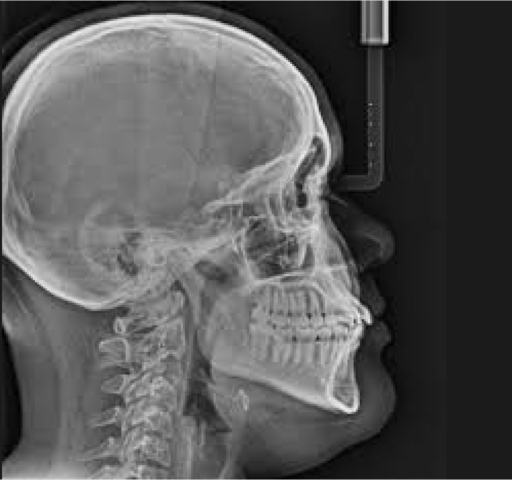

Desde que se descubrieron los rayos X en 1895, se observó que éstos podían producir efectos nocivos para la salud.

• RAYOS X-En 1901

RAYOS X-En 1901

el doctor Montoya Flórez, padre de la cirugía en Colombia, trajo a Medellín el primer equipo de rayos X con el cual se realizó la primera radiografía en Colombia